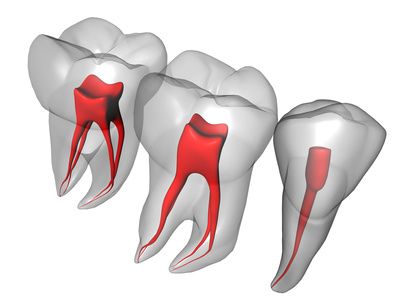

Ενδοδοντία είναι ο τομέας της οδοντιατρικής, που ασχολείται με τη διάγνωση και θεραπεία των παθήσεων του πολφού, δηλαδή του εσωτερικού του δοντιού. Με απλά λόγια ενδοδοντολόγος / ενδοδοντιστής, είναι ο οδοντίατρος που το κύριο αντικείμενό ενασχόλησής του είναι οι απονευρώσεις δοντιών.

Με την απονεύρωση ο ενδοδοντολόγος αφαιρεί το νεκρό ή μολυσμένο πολφό, όπως και τα νεύρα του δοντιού. Αφού επεξεργαστεί και καθαρίσει πλήρως το δόντι σε 2 ή 3 συνεδρίες,ανάλογα με το βαθμό δυσκολίας του δοντιού, στη συνέχεια εμφράσσονται οι ριζικοί σωλήνες με ένα ειδικό υλικό που λέγεται γουταπέρκα. Σκοπός της έμφραξης των ριζικών σωλήνων είναι η αποφυγή επαναμόλυνσης του πολφού. Στη συνέχεια ακολουθεί η αποκατάσταση του δοντιού με σφράγισμα ή στεφάνη ανάλογα με το έκταση της οδοντικής βλάβης.